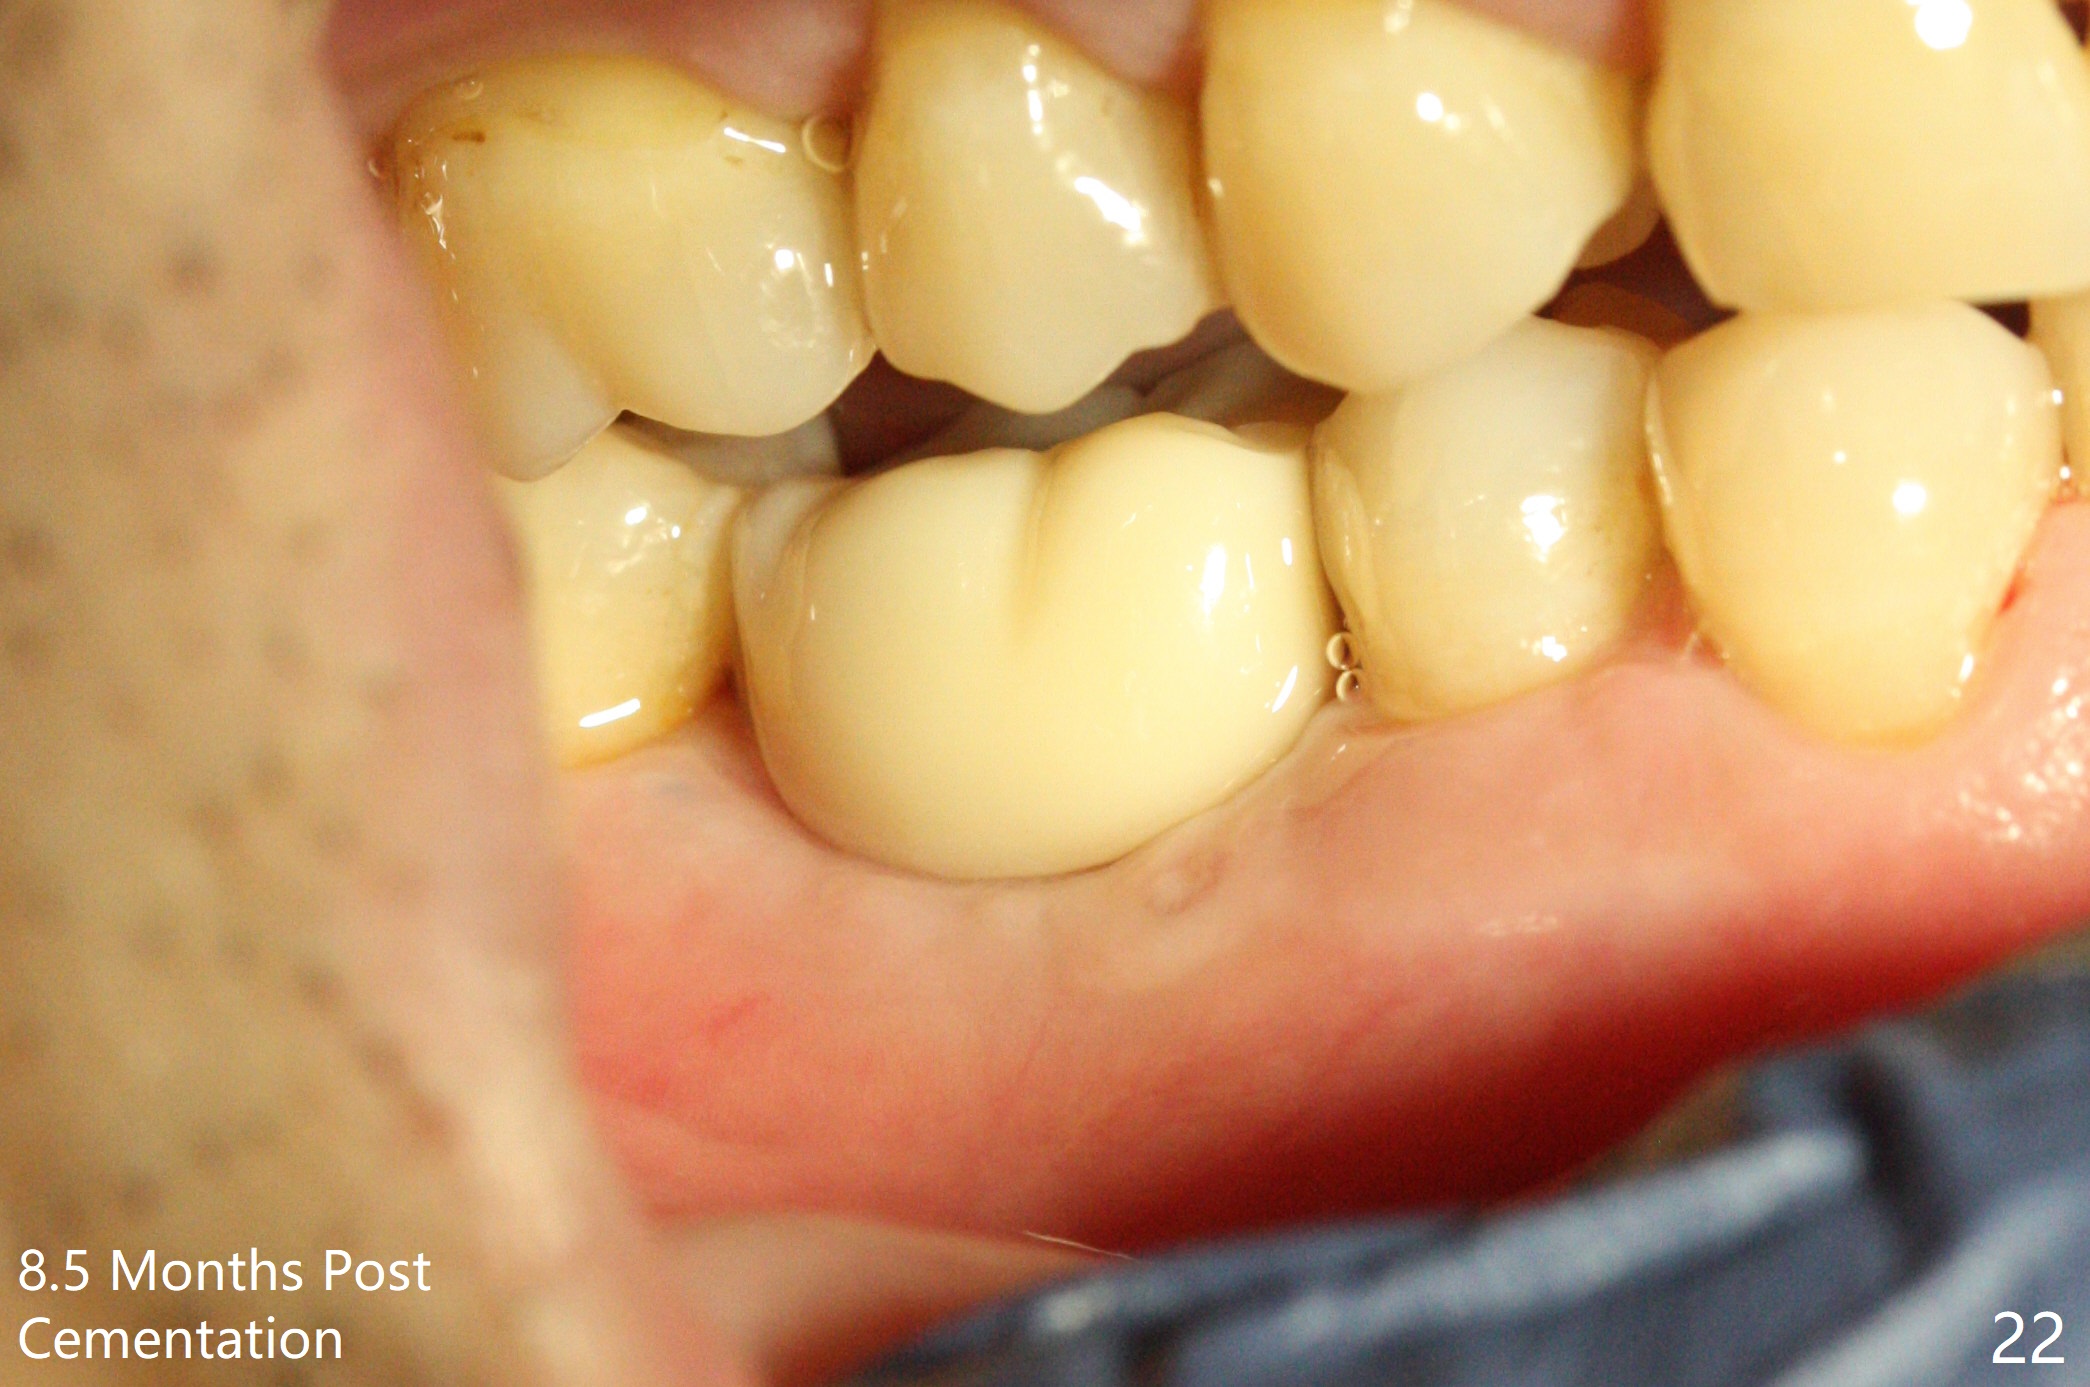

Three weeks later (5.5 months postop), a permanent crown tries in with healthy keratinized gingiva (Fig.18). The provisional keeps normal gingival bed (Fig.19), while the abutment forms tissue cuff (Fig.20). After cementation, PA shows bone regeneration (Fig.21). The gingiva remains healthy 8.5 months post cementation (Fig.22). Bone density around the implant increases 1 year 2 months post cementation (Fig.24). The gingiva remains healthy 2 years 4 months post cementation (Fig.25).